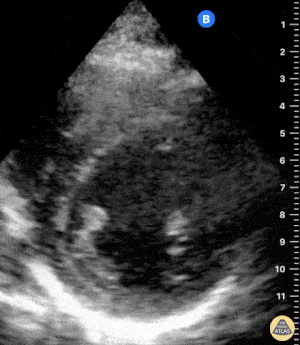

Sağ ventrikül fonksiyonunun değerlendirilmesi

Sağ ventrikül, önceki bölümde anlatılan temel kardiyak pencereler kullanılarak değerlendirilebilir. Normalde sağ ventrikül düşük basınçlı bir odacıktır ve sol ventriküle kıyasla daha küçük görünür.

Sağ ventrikül disfonksiyonunda özellikle şu bulgulara bakılır:

Sağ ventrikül dilatasyonu

Septal bombeleşme (septal bowing)

Kısa aks görüntüsünde, pulmoner arter basıncının artmasına bağlı olarak sağ ventrikül genişledikçe interventriküler septum sol kalbe doğru bombeleşir. Bu durum sol ventrikülde D-şekilli görünüm (D-sign) oluşturur.

Apikal dört boşluk görüntüsünde sağ ventrikül normalde sol ventrikülün yaklaşık üçte ikisi büyüklüğünde olmalıdır. Eğer iki ventrikül aynı boyutta görünüyorsa bu durum anormal kabul edilir ve dilatasyon düşündürür.